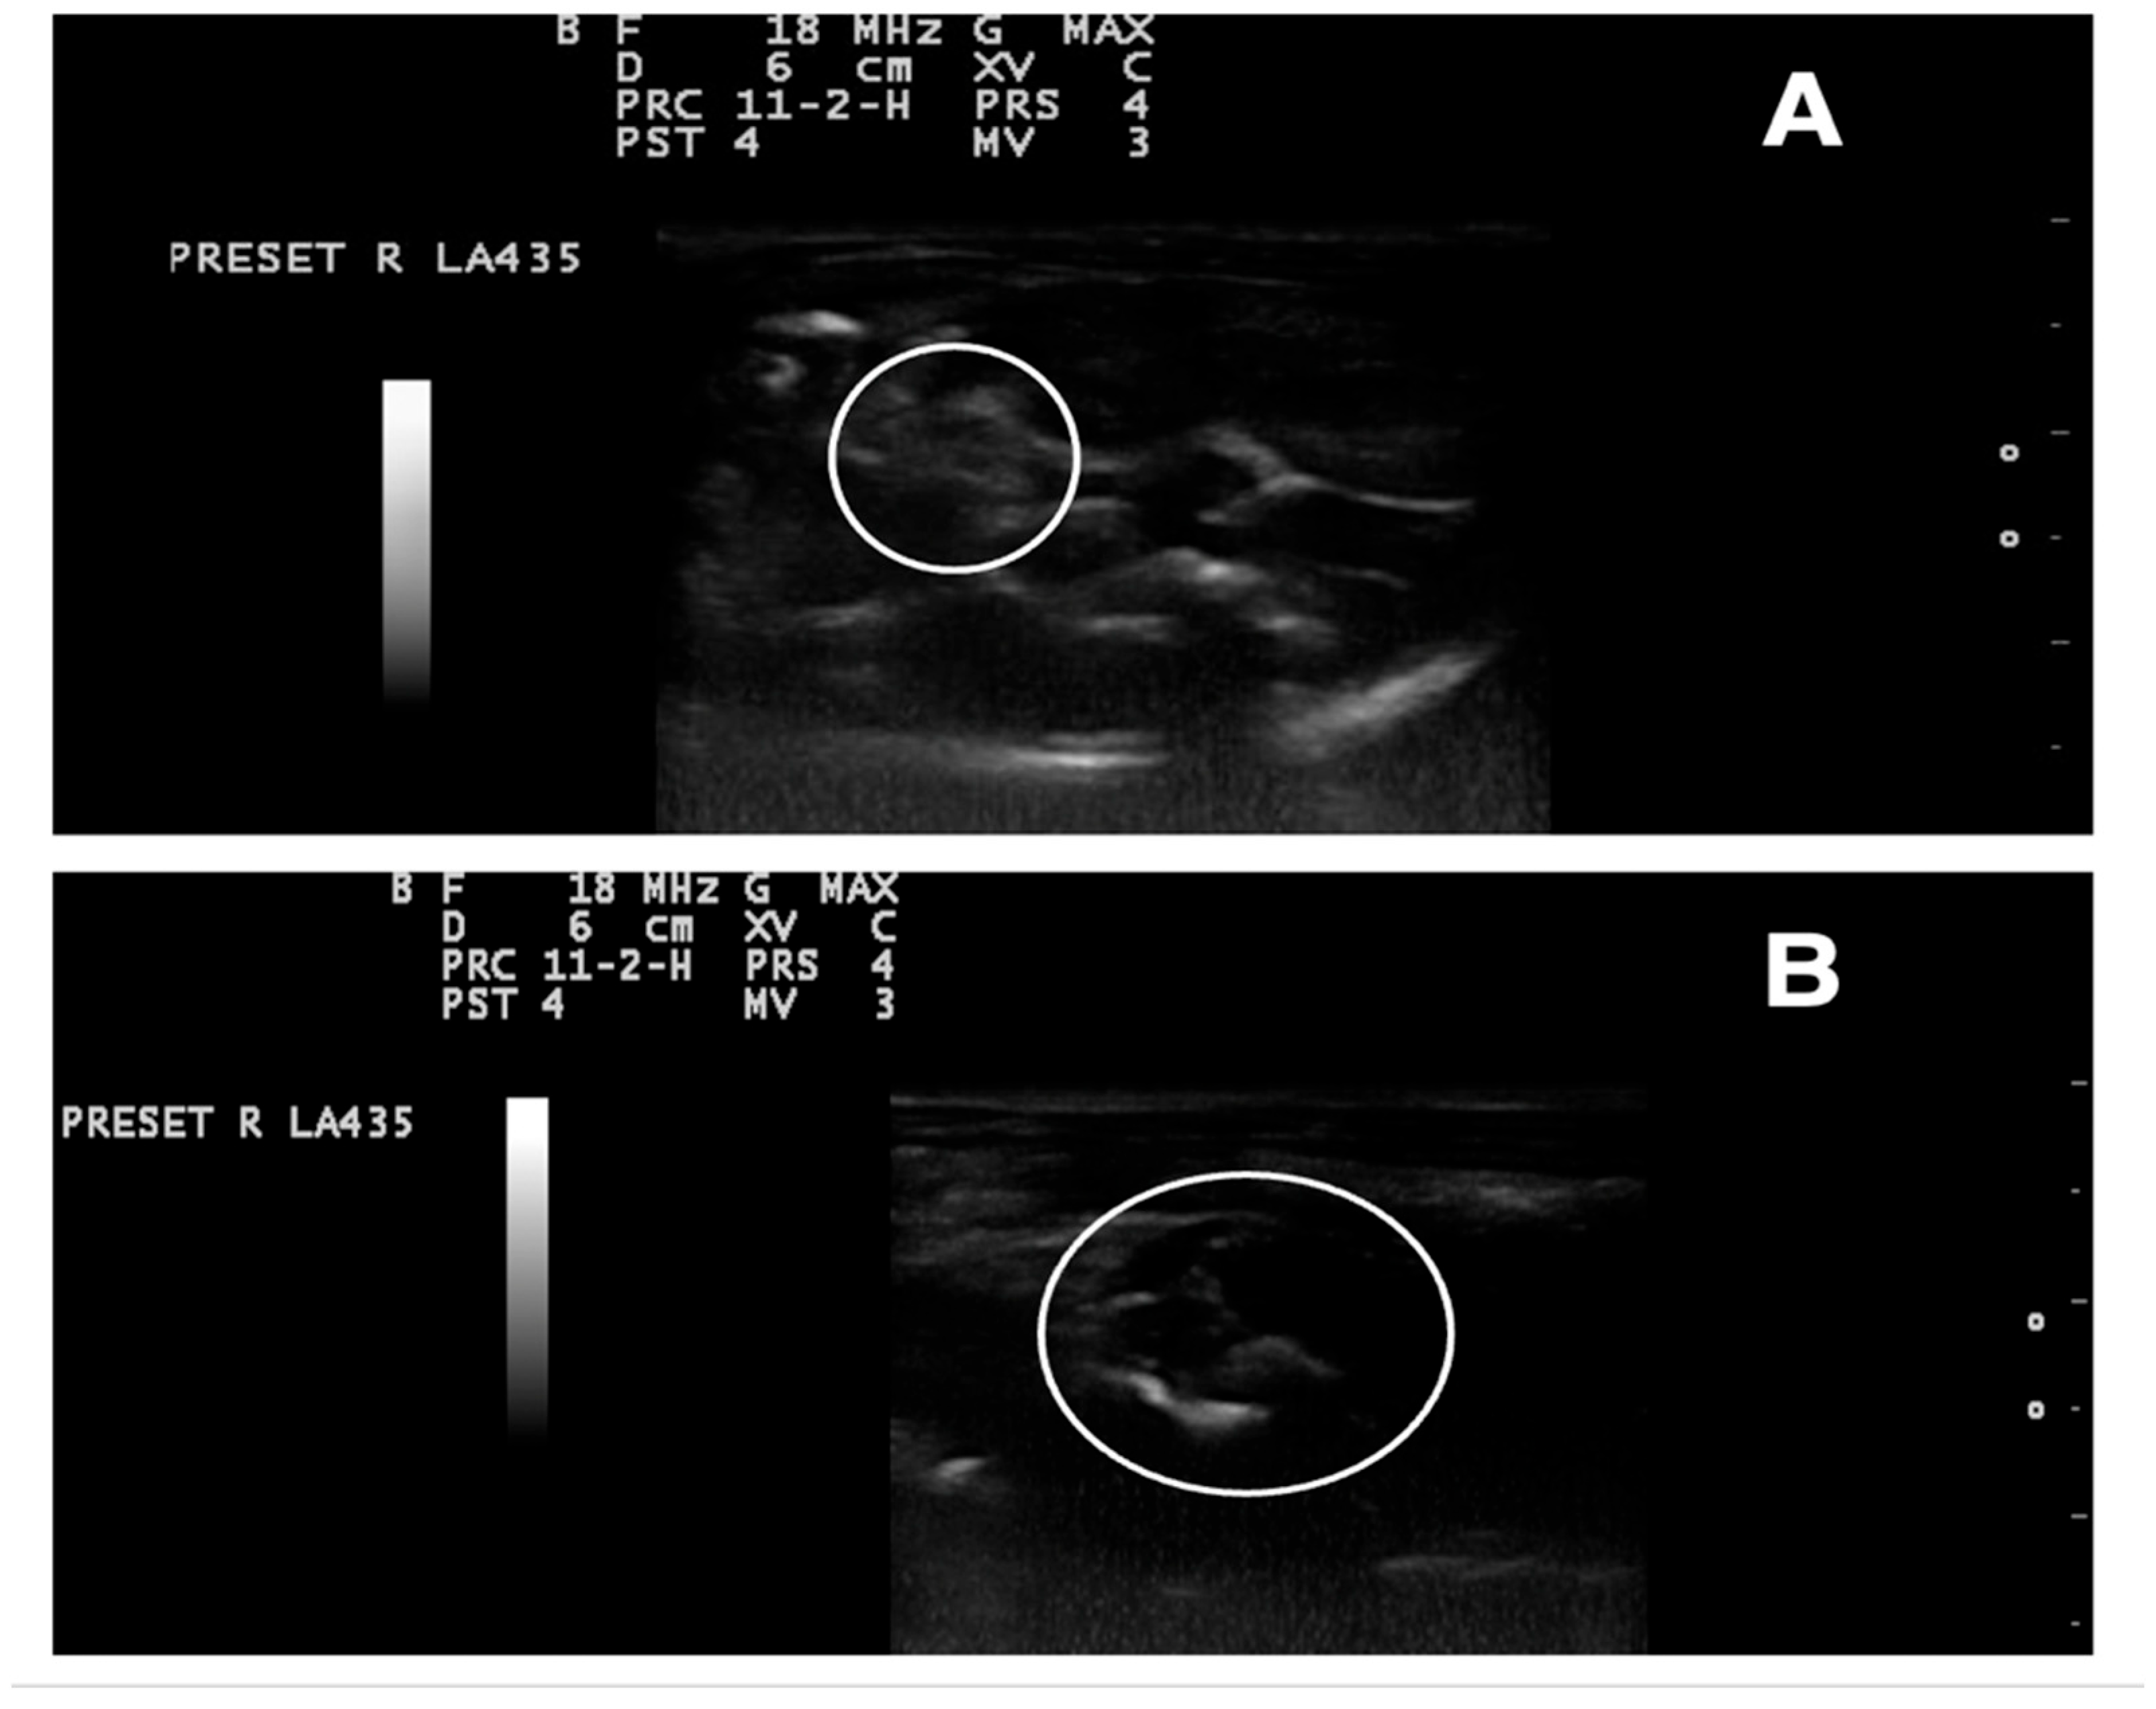

2.9. Ultrasound Examination

3.9. Ultrasonography Examination